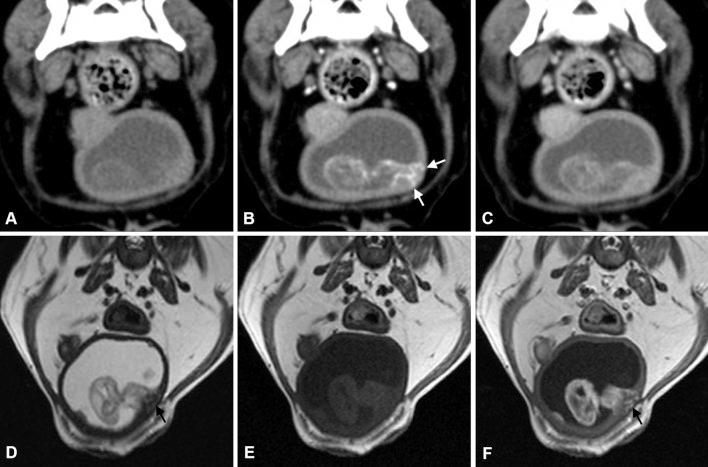

This study described high-field magnetic resonance imaging (MRI) and computed tomography (CT) characteristics of muscle-invasive bladder transitional cell carcinoma (TCC) in two dogs. Ultrasonography revealed a urinary bladder mass with ambiguous result about invasion to the muscular layer. Contrast-enhanced CT showed that the bladder wall in which the mass was attached was more intensely enhanced than the normal bladder walls, supporting invasion to the muscular layer. The mass revealed an intermediate signal intensity with interruption of the hypointense muscular layer on T2-weighted MRI and showed greater enhancement compared with the normal bladder wall on postcontrast T1-weighted images. T2-weighted MRI, postcontrast T1-weighted MRI and contrast-enhanced dual-phasic CT were useful for evaluating muscle-invasive bladder TCC in dogs.